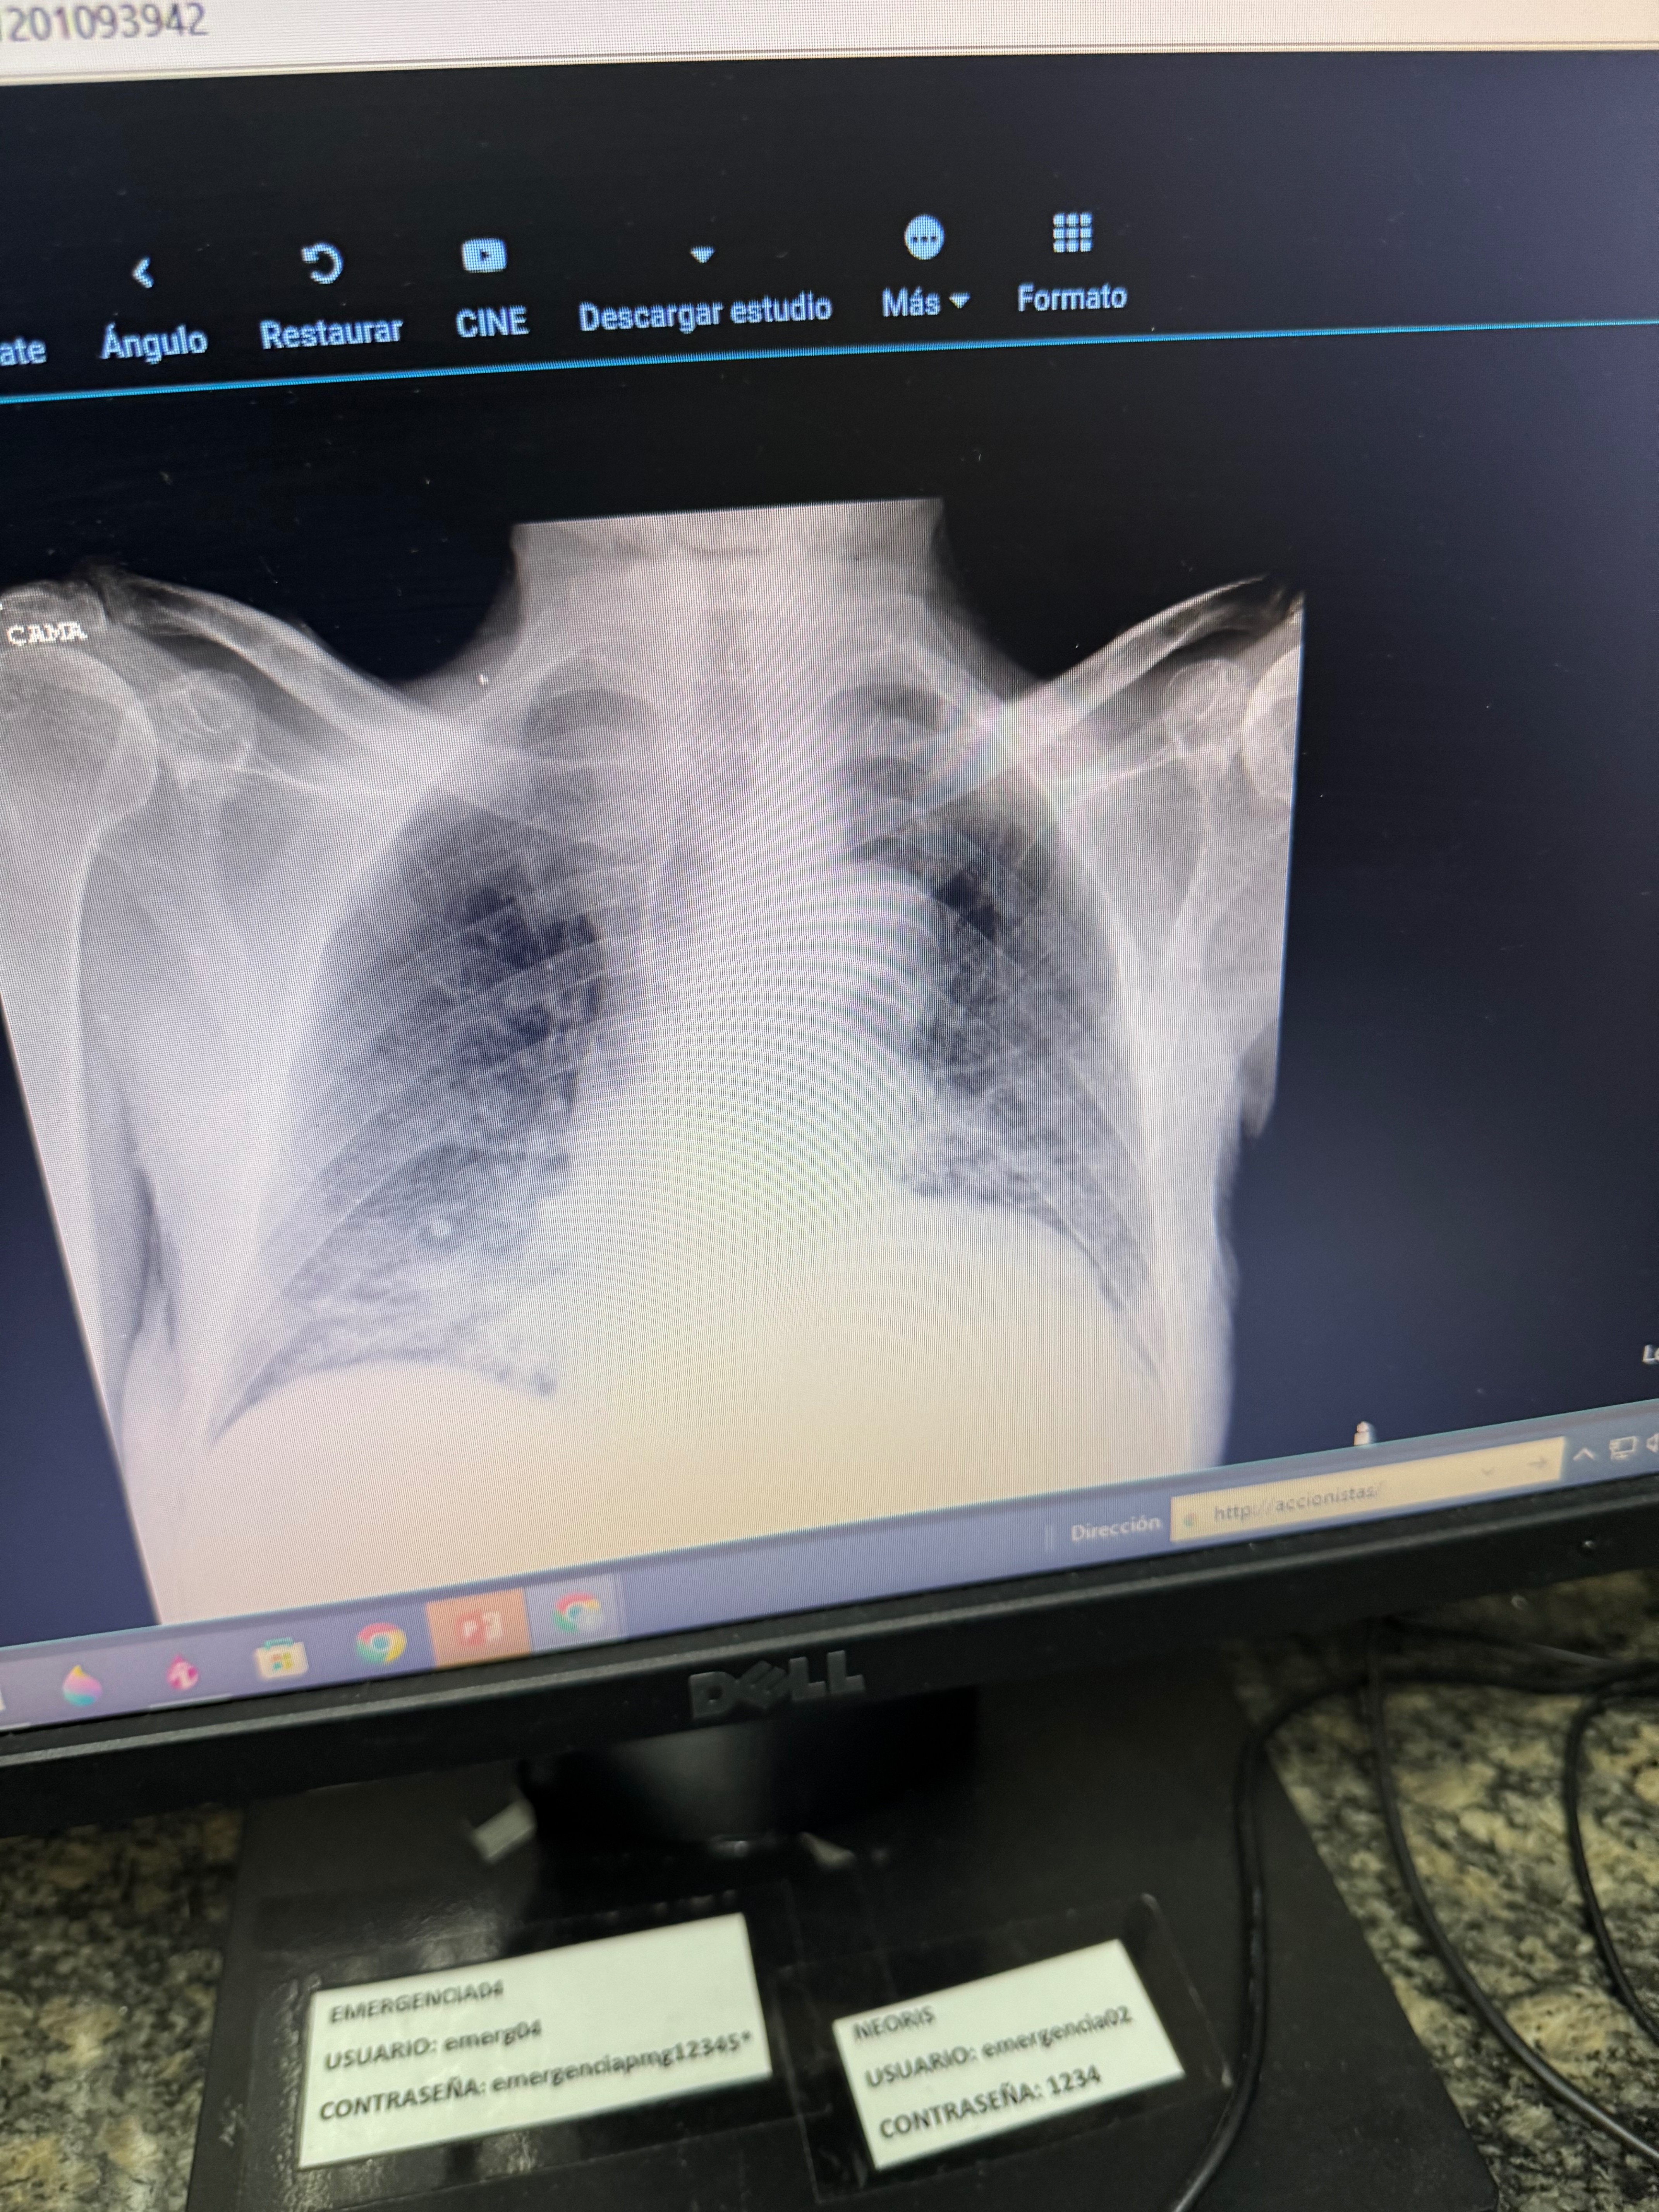

My dad, Nelson, 83 years old with dementia has been in the hospital for the past couple of days in Venezuela, where my parents have been staying since May. He suddenly became ill and was diagnosed with a severe respiratory infection (influenza B and pneumonia) as well as gastric bleeding. The bleeding caused fluid to go into his lungs, and his condition became critical very quickly.

Mi papá, Nelson, de 83 años y con demencia, ha estado hospitalizado durante los últimos días en Venezuela, donde mis padres se encuentran desde el pasado mes de mayo. Se enfermó de manera repentina y fue diagnosticado con una infección respiratoria severa (influenza B y neumonía), además de un sangrado gástrico. El sangrado hizo que líquido pasara a sus pulmones, y su condición se volvió crítica muy rápidamente.